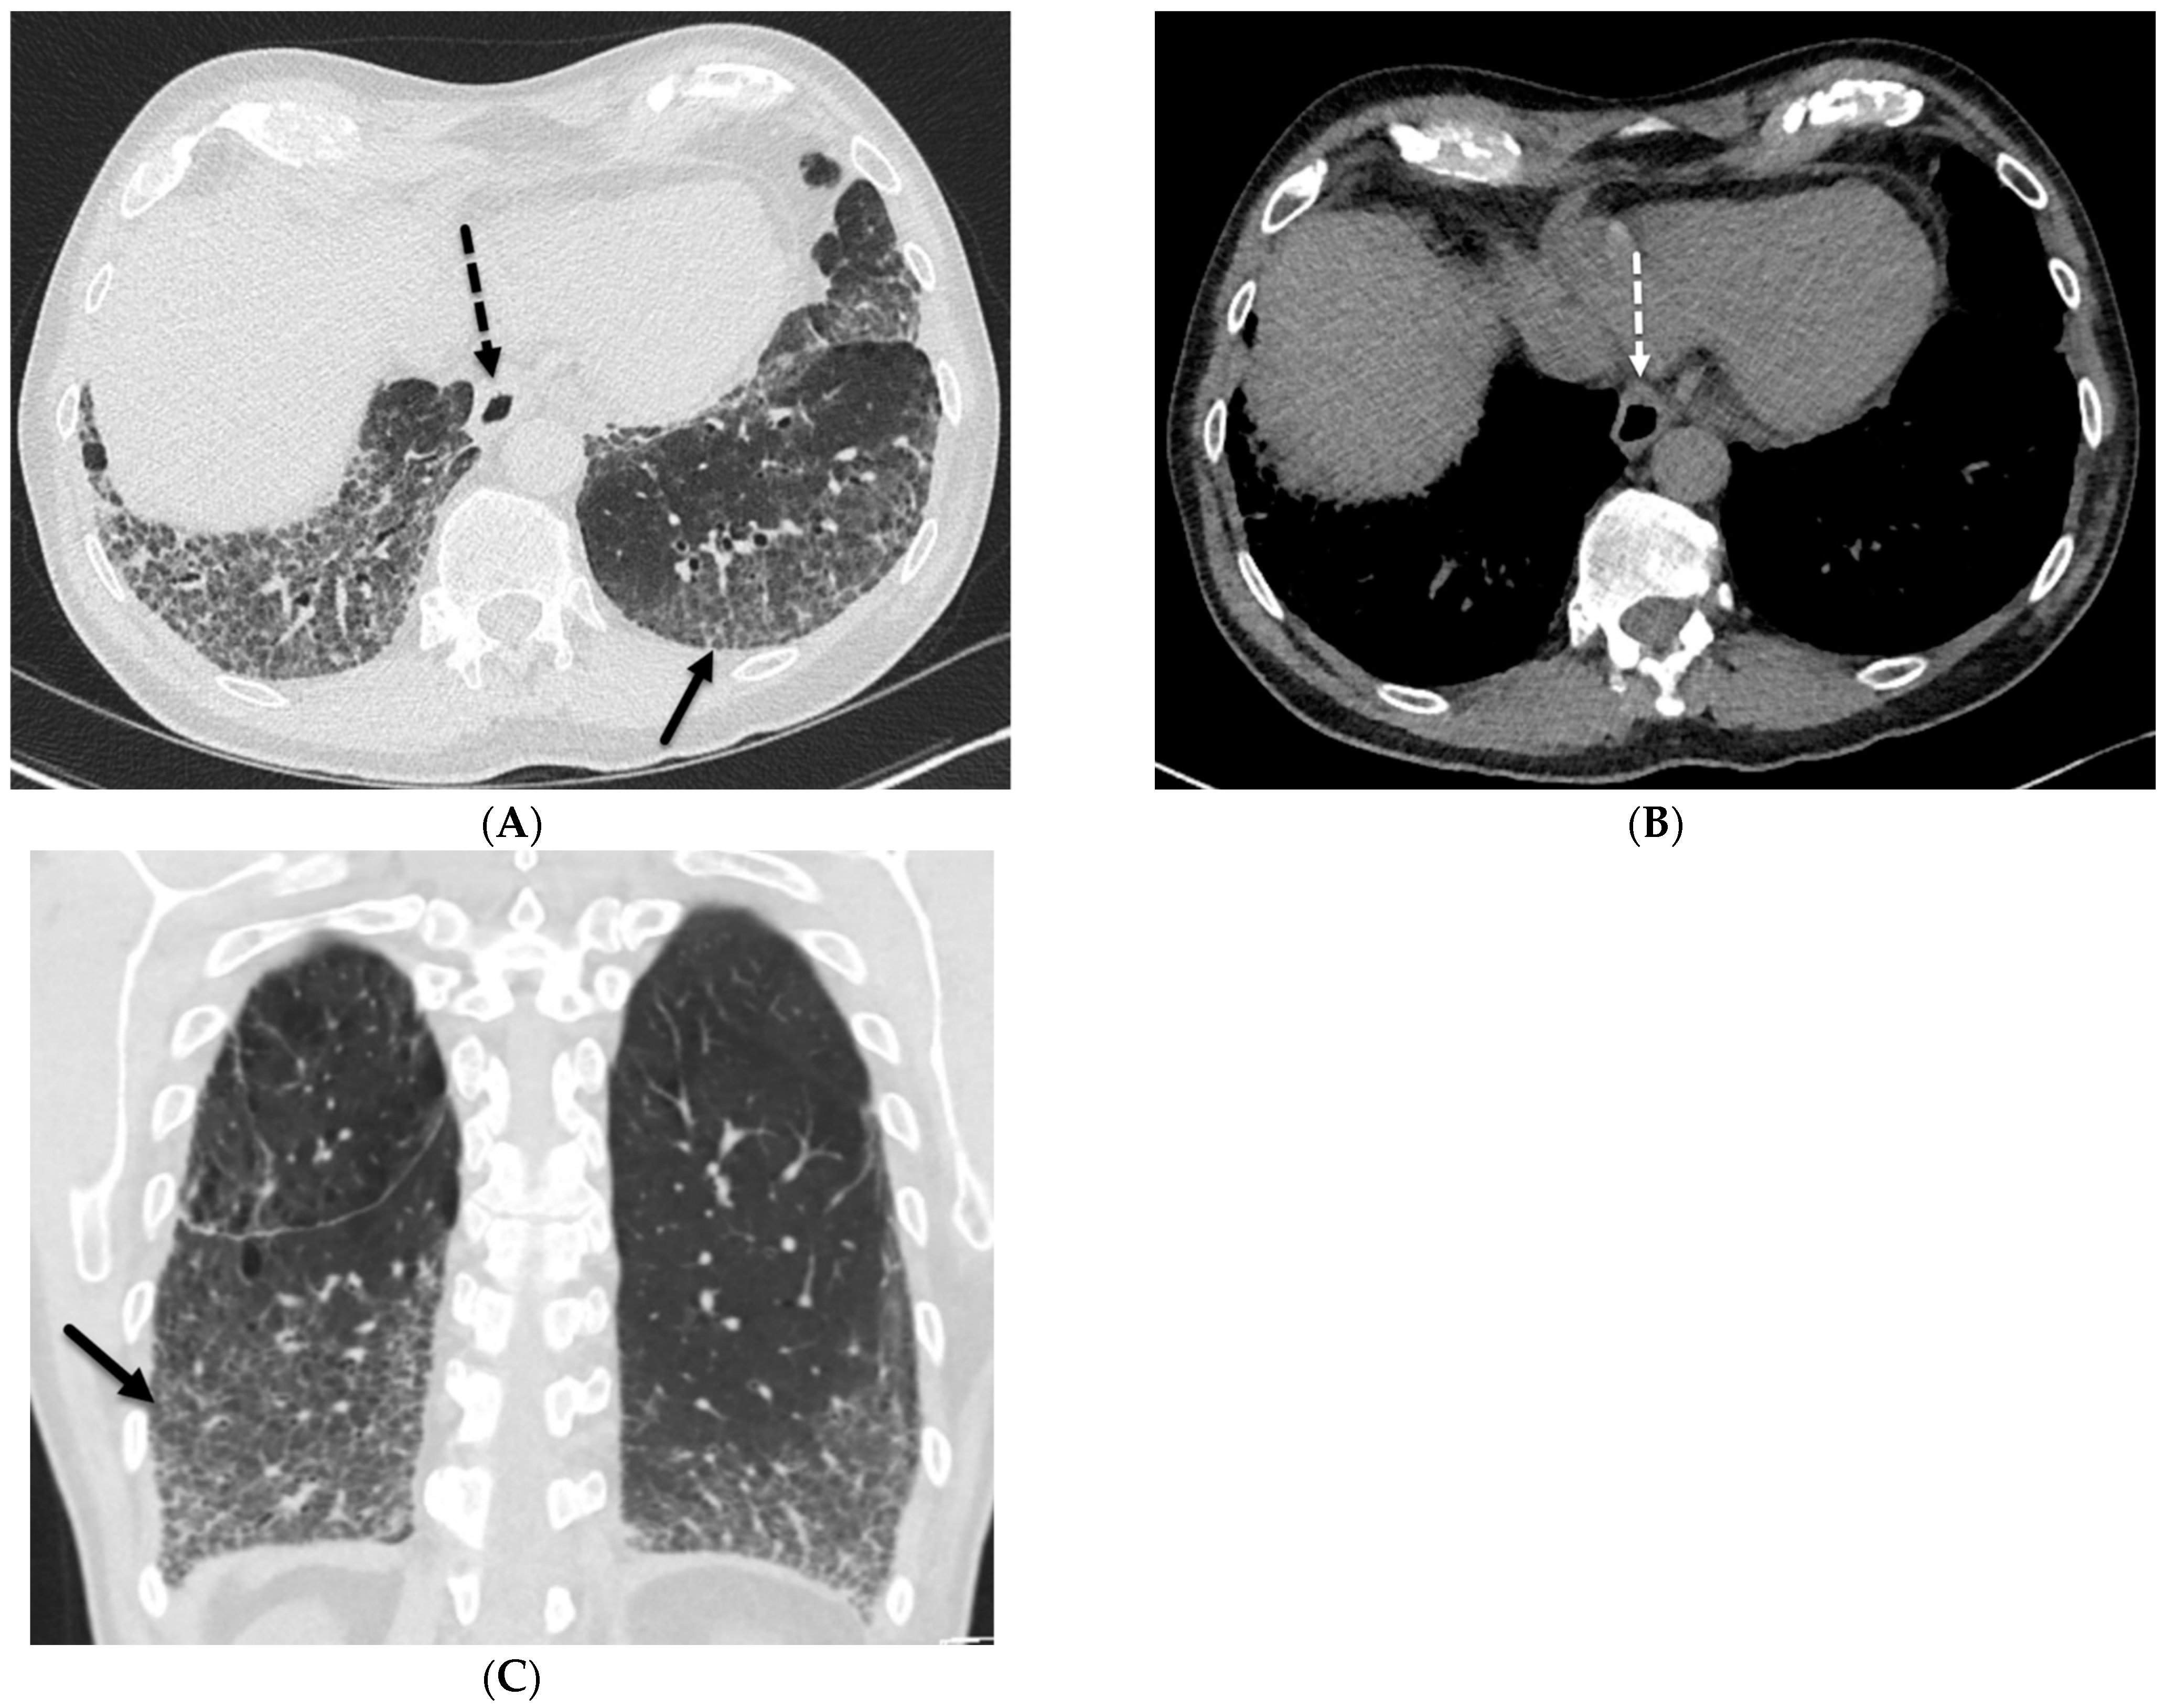

6. Depositional

6.2. Pulmonary Alveolar Proteinosis (PAP)

6.3. Amyloidosis

8.1. Diffuse Alveolar Hemorrhage (DAH)

8.4. Erdheim Chester Disease (ECD)